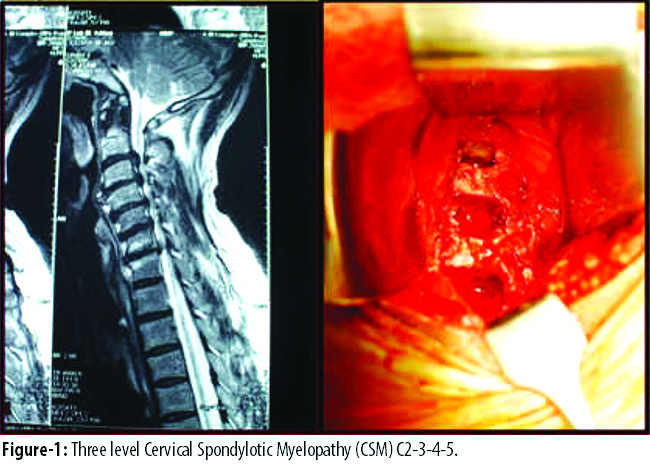

Anterior cervical approach is a common approach when compressive pathology is anterior and usually less than three levels or spine is in kyphosis. In the present study in 48 cases anterior cervical surgery was done, disc excision and bone grafting with plate fixation in 26 and corpectomy with cage and plate fixation in 21. Anterior pathology up to three levels was approached anteriorly with anterior cervical discectomy and fusion (ACDF) (Figures-1-2) or anterior cervical corpectomy and fusion (ACCF) (Figure-3).